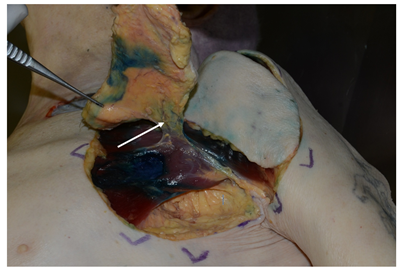

In the second phase, the cadaver was thawed out at room temperature and then placed in dorsal decubitus to dissect the integuments. For this dissection, a superficial incision was made on the lateral, caudal and cranial margins of the cutaneous perforasome, making sure not to breach the muscle layer. Next, the superficial plane was separated from the muscle layer from the periphery to the center of each perforasome. This dissection was performed meticulously so as to prevent damaging the satellite veins accompanying each perforating artery. During this procedure, the perforators were dissected and inventoried based on their location, dimensions, orientation, frequency and size of the cutaneous perforasome. Dissection of the largest perforators was then continued through the muscle while preserving the integrity of the pectoralis major muscle. The superficial layer (perforator flap) was then harvested completely with its pedicle (Figure 3).

Figure 3 Dissection of the clavicular and pectoral branches of the left thoracoacromial artery (white arrow).